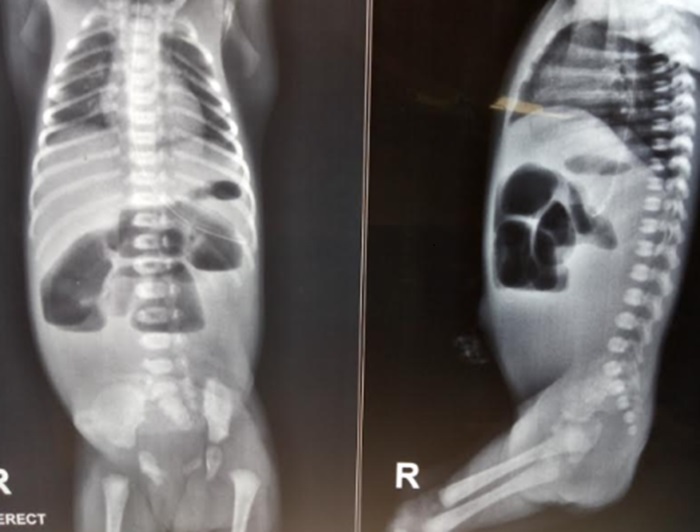

The baby was initially stabilized with intravenous fluid boluses and triple antibiotics were started. The baby was catheterized and a nasogastric tube was passed and 20 ml bilious fluid aspirated. After stabilization, an abdominal radiograph was done that demonstrated a few dilated small bowel loops in the central abdomen with air-fluid levels(Fig. 2). Routine blood investigations were normal except for raised urea (48 mg/dl) and creatinine (0.8 mg/dl). The baby was planned for laparotomy and revealed a type IV intestinal atresia as well as malrotation (DJ to right of the spine). Three atresias were found, the first 25 cm distal to DJ flexure, second 14 cm distal to the first atresia, and third 15 cm proximal of ileocecal junction (Fig. 3).

Figure 2

X-ray abdomen showing few dilated loops and air-fluid levels.